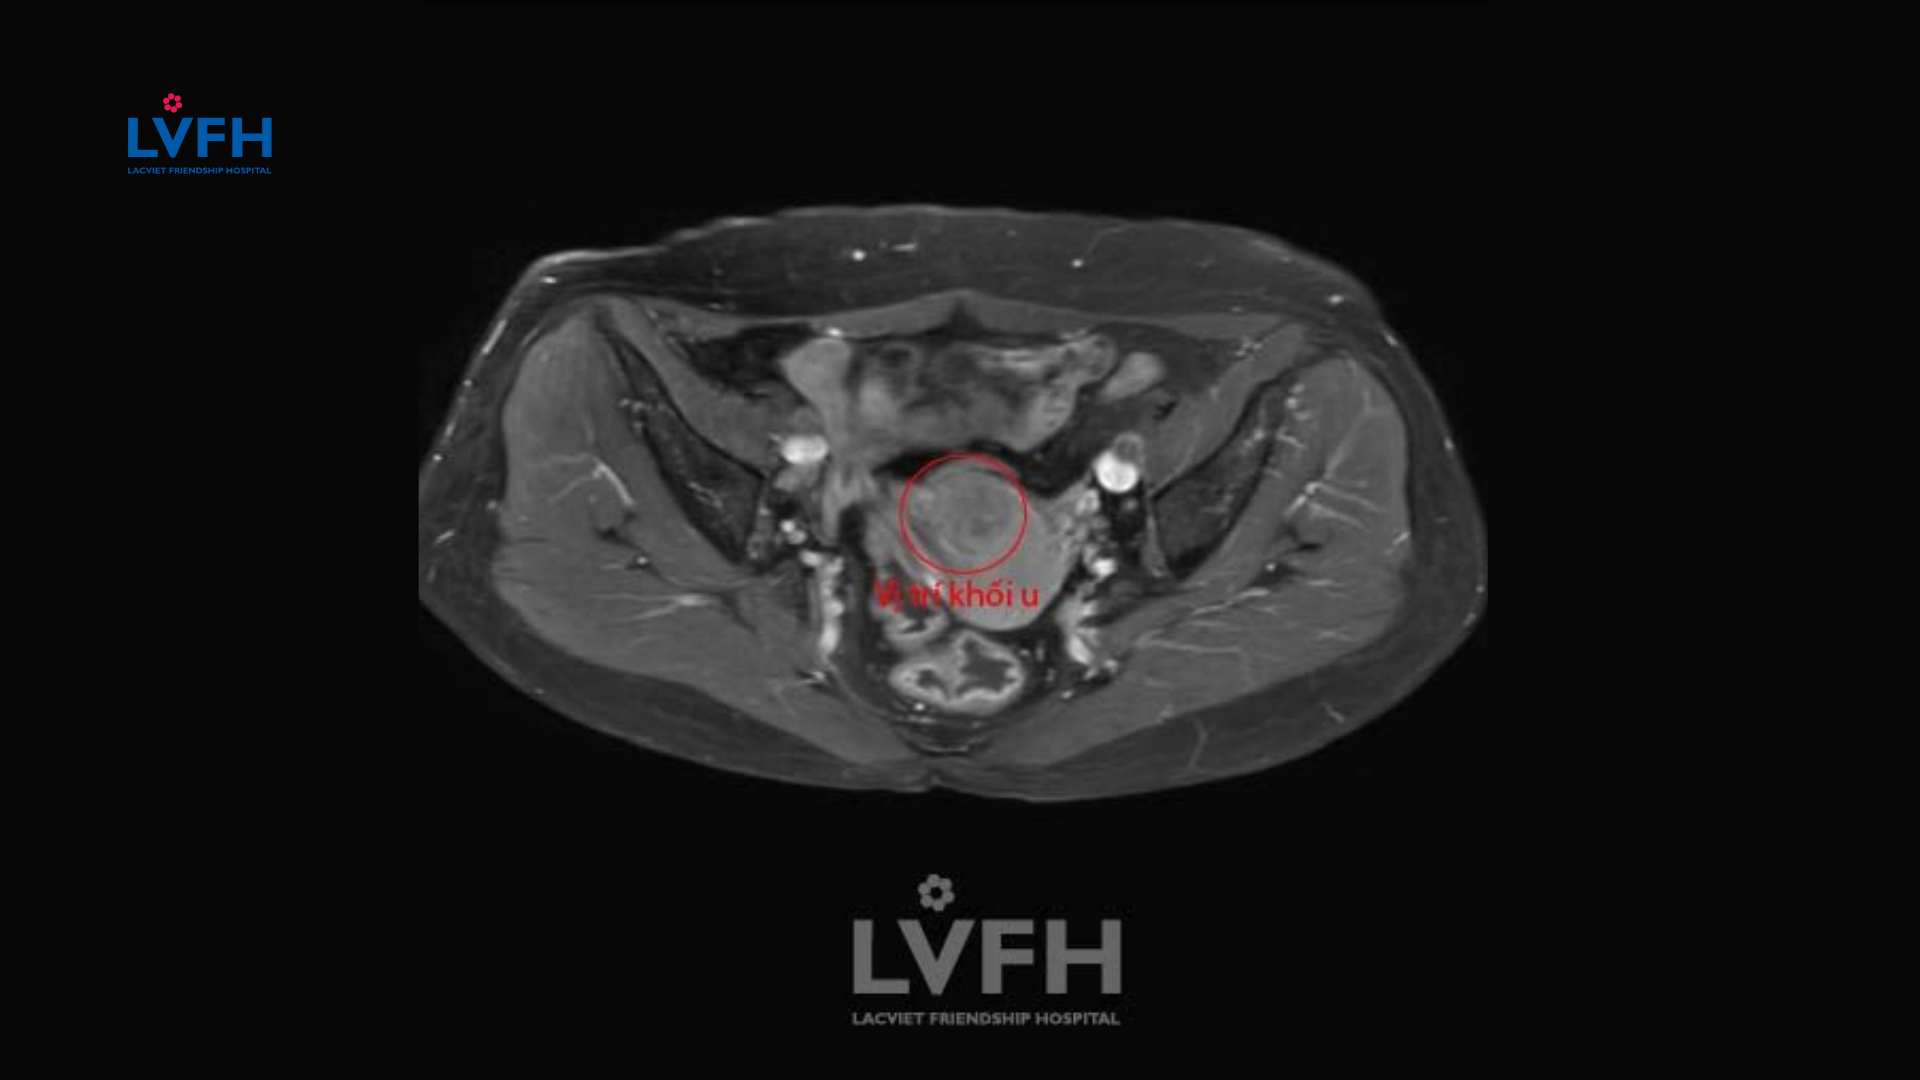

• Chụp MRI, CT Scan hoặc PET-CT: Các kỹ thuật hình ảnh chuyên sâu này giúp bác sĩ đánh giá chi tiết kích thước khối u, mức độ xâm lấn vào các mô xung quanh tiểu khung và kiểm tra tình trạng di căn hạch bạch huyết.

7. Ca lâm sàng thực tế tại Bệnh viện Lạc Việt

Chúng tôi đã tiếp nhận và điều trị thành công cho nhiều chị em mắc ung thư cổ tử cung. Một trường hợp điển hình là bệnh nhân phát hiện bệnh ở giai đoạn IIA nhờ tầm soát định kỳ tại bệnh viện.

Sau khi thực hiện phác đồ kết hợp phẫu thuật nội soi và xạ trị tại Bệnh viện Lạc Việt, hiện tại sức khỏe chị đã hoàn toàn ổn định, kết quả xét nghiệm không còn dấu hiệu tái phát ung thư cổ tử cung sau 3 năm theo dõi.